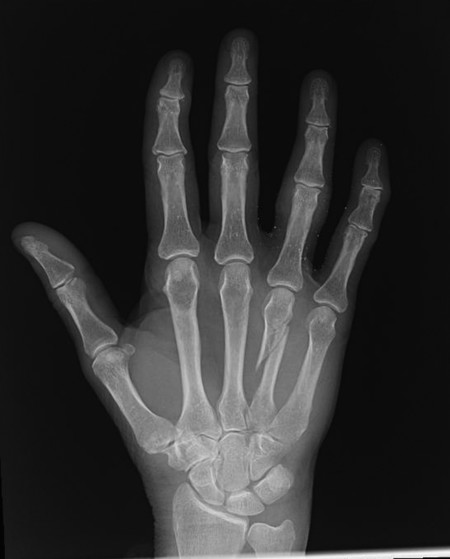

Hand surgeons, young and old, like to fix fractures. However, it is important to be selective and to identify cases where nonoperative management may be preferable (Fig. 14‑6). Many hand fractures can be treated conservatively as long as the fracture is stable, minimally displaced with no rotation or scissoring.